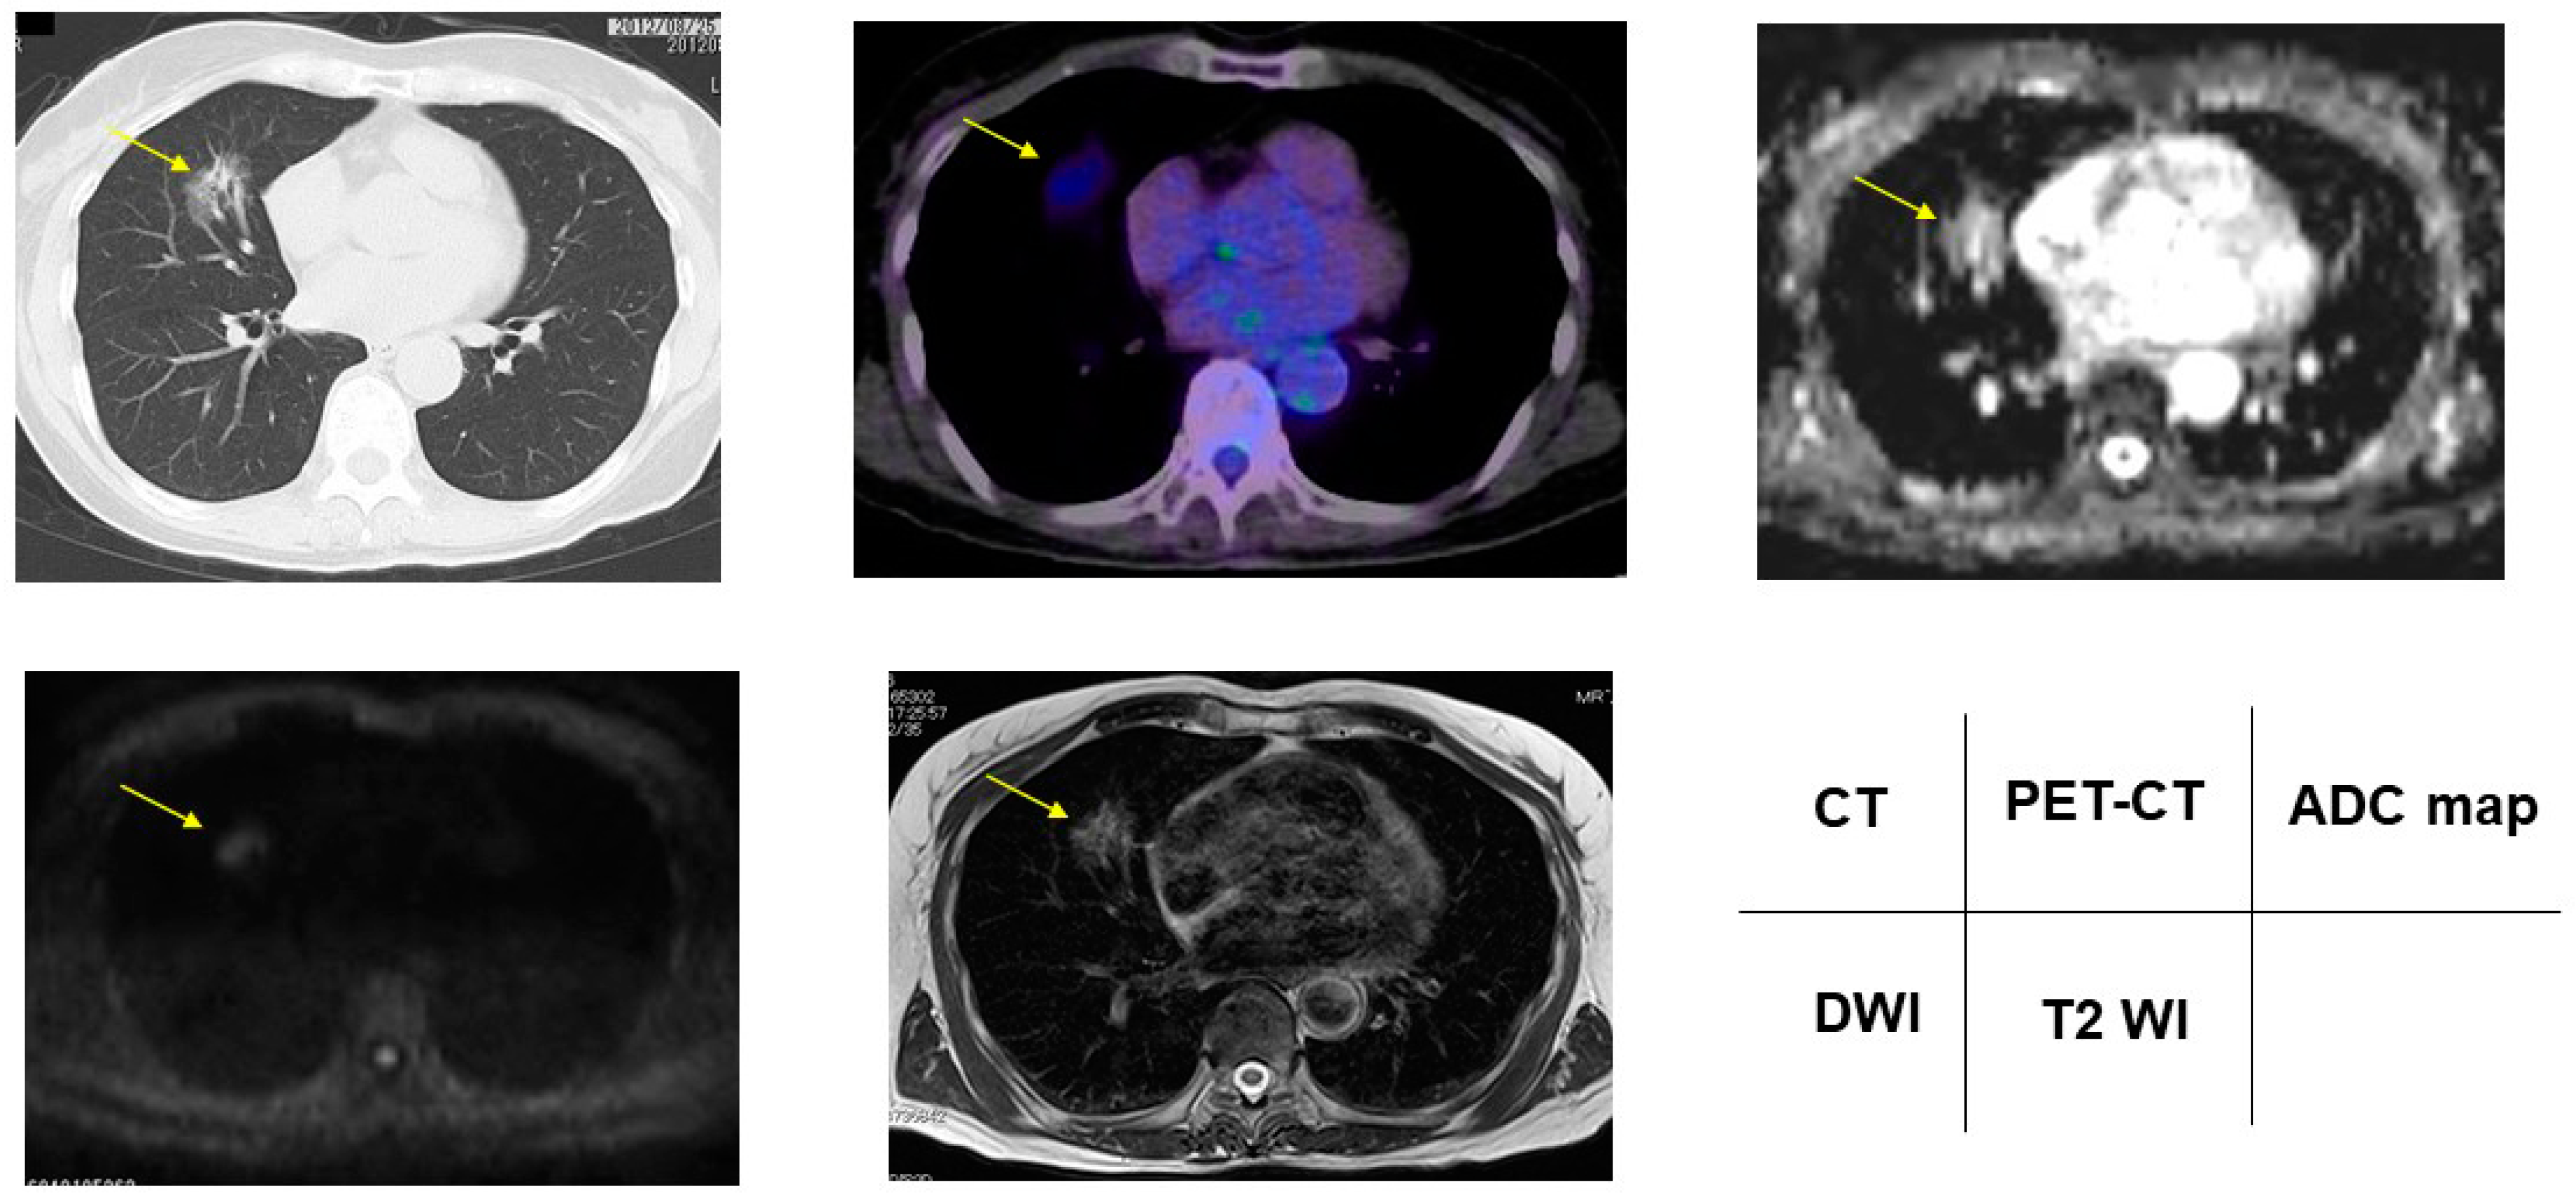

3.2. Radiologic Presentations of CT, FDG-PET/CT, DDS of DWI, ADC Map and T2WI in PNMs